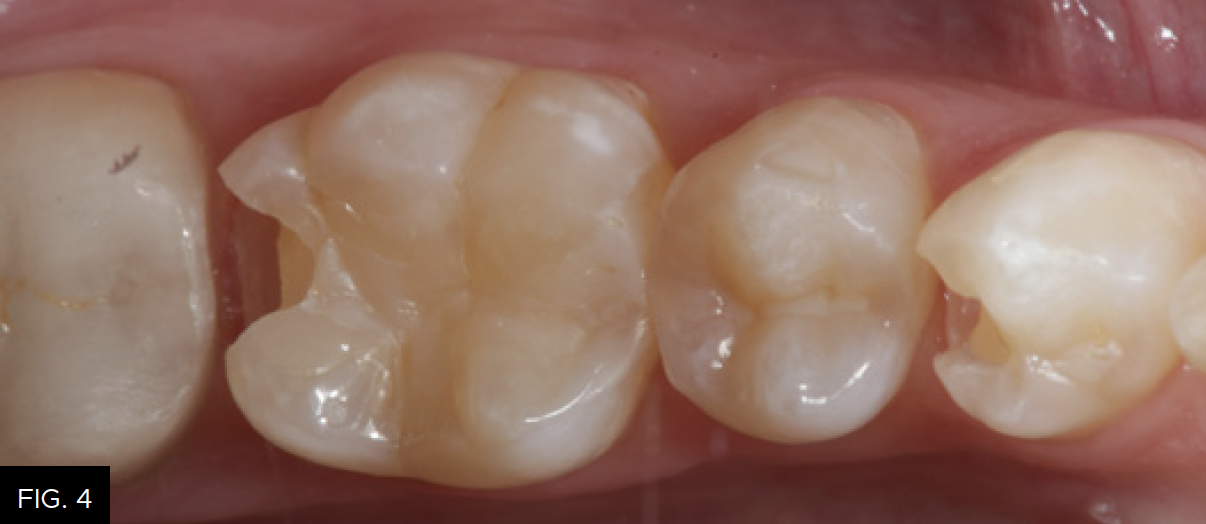

The patient shown in FIG. 1 presented with radiographic decay (FIG.2 and 3) on the distal surfaces of tooth numbers 19 (36) and 21 (34).

After removal of the decay and creation of the cavity outline form, the operative area is isolated with an Isolite (Isolite Systems) in preparation for the restorative process. (FIG. 4)